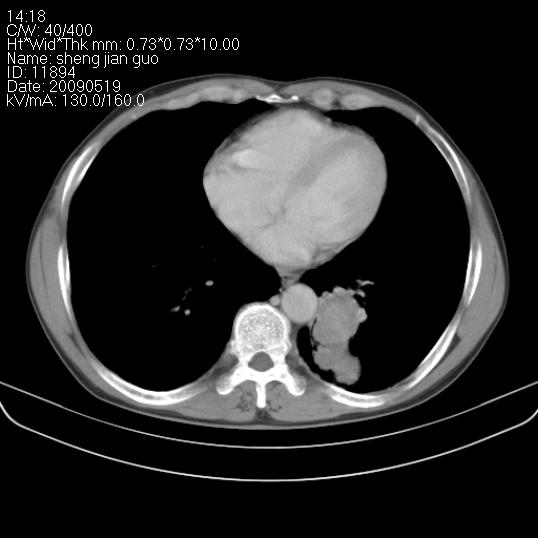

以下是引用zjzjr在2009-5-19 17:25:00的发言:[br]支持楼主考虑,另左肺下叶阻塞性炎症。

以下是引用zhao_bin2008在2009-5-19 17:48:00的发言:[br]支持左肺下叶周围型肺癌并阻塞性肺炎。

以下是引用zsl6918在2009-5-20 7:10:00的发言:[br]左侧中心型肺癌!